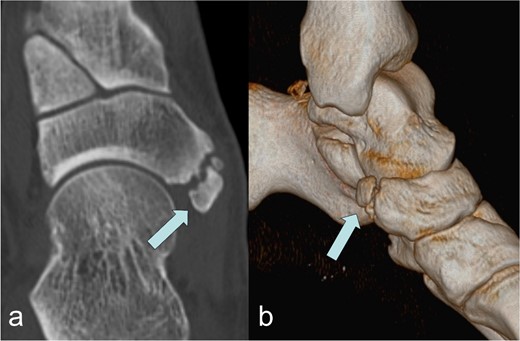

A 53-year-old man with a body mass index of 22.3 kg/m2 reported severe, load-dependent pain (6 out of 10 on the VAS) in the left foot, which had increased over the past two months. Light jogging as a recreational sport was no longer possible due to pain, and no trauma was recalled. Clinically, there was a mild pes planovalgus, with slight swelling and warmth medioplantarly and distal to the medial malleolus along the course of the tibialis posterior tendon. A marked point tenderness was noted, and forced dorsiflexion was severely painful. Conventional radiographs showed a triangular Type II Os tibiale externum at the typical site, measuring approximately 10.5 x 6 mm (Fig. 1a and b). Additional CT imaging in the axial plane with coronal reconstruction and subsequent 3D reconstruction (Fig. 2a and b) revealed a Type II Os tibiale externum with a distinct synchondrosis gap to the navicular bone. An MRI showed central inflammatory reaction in the synchondrosis and significant perifocal soft tissue edema of the Os tibiale externum with involvement of the tibialis posterior tendon, with no tendon rupture detected (Fig. 3a–d).

Os tibiale externum Type II in the coronal T1-weighted MRI scan (a), inflammatory reaction/tendinosis at the insertion of the tendon of the tibialis posterior muscle visualized in the heavily T2-weighted, fat-suppressed MRI scans (b and c), synchondrosis between the Os tibiale externum Type II and Os naviculare with central and perifocal edema visualized in the sagittal heavily T2-weighted, fat-suppressed MRI scan (d); each marked with an arrow.